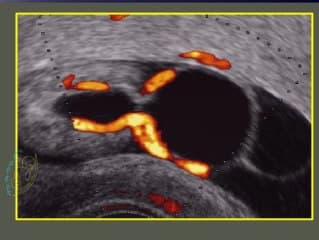

Très belles images didactiques d'un diagnostic rare, celui des fistules Porto-sus hépatiques. L'auteur à partir d'une série de 12 cas fait le point sur le diagnostic et la conduite à tenir à partir des complications observées.